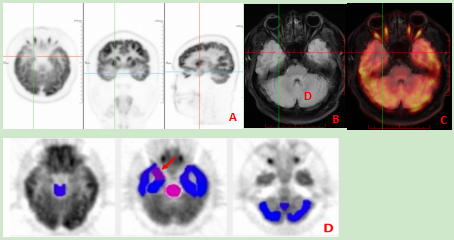

对于神经系统疾病,如癫痫、帕金森病、阿尔兹海默症等,PET/MR的多探针多模态显像为疾病诊断提供了更丰富的分子代谢、组织结构及生理信息,有助于疾病的早期诊断和治疗监测。上海市第一人民医院(南部)核医学科使用的联影的NeuroQ软件能提供一站式的AI影像智能分析,在脑FDG代谢数据分析、癫痫的预后分析及淀粉样蛋白的定量研究等方面具有重要的应用价值。

病例3:局灶性癫痫患者PET/MR图像。A18F-FDG PET示右颞叶内侧份局灶性代谢减低;BMRI右颞叶结构未见明确异常;CPET/MR融合图像;DNeuroQ软件分析提示右颞叶FDG摄取明显低于正常脑(箭头)。